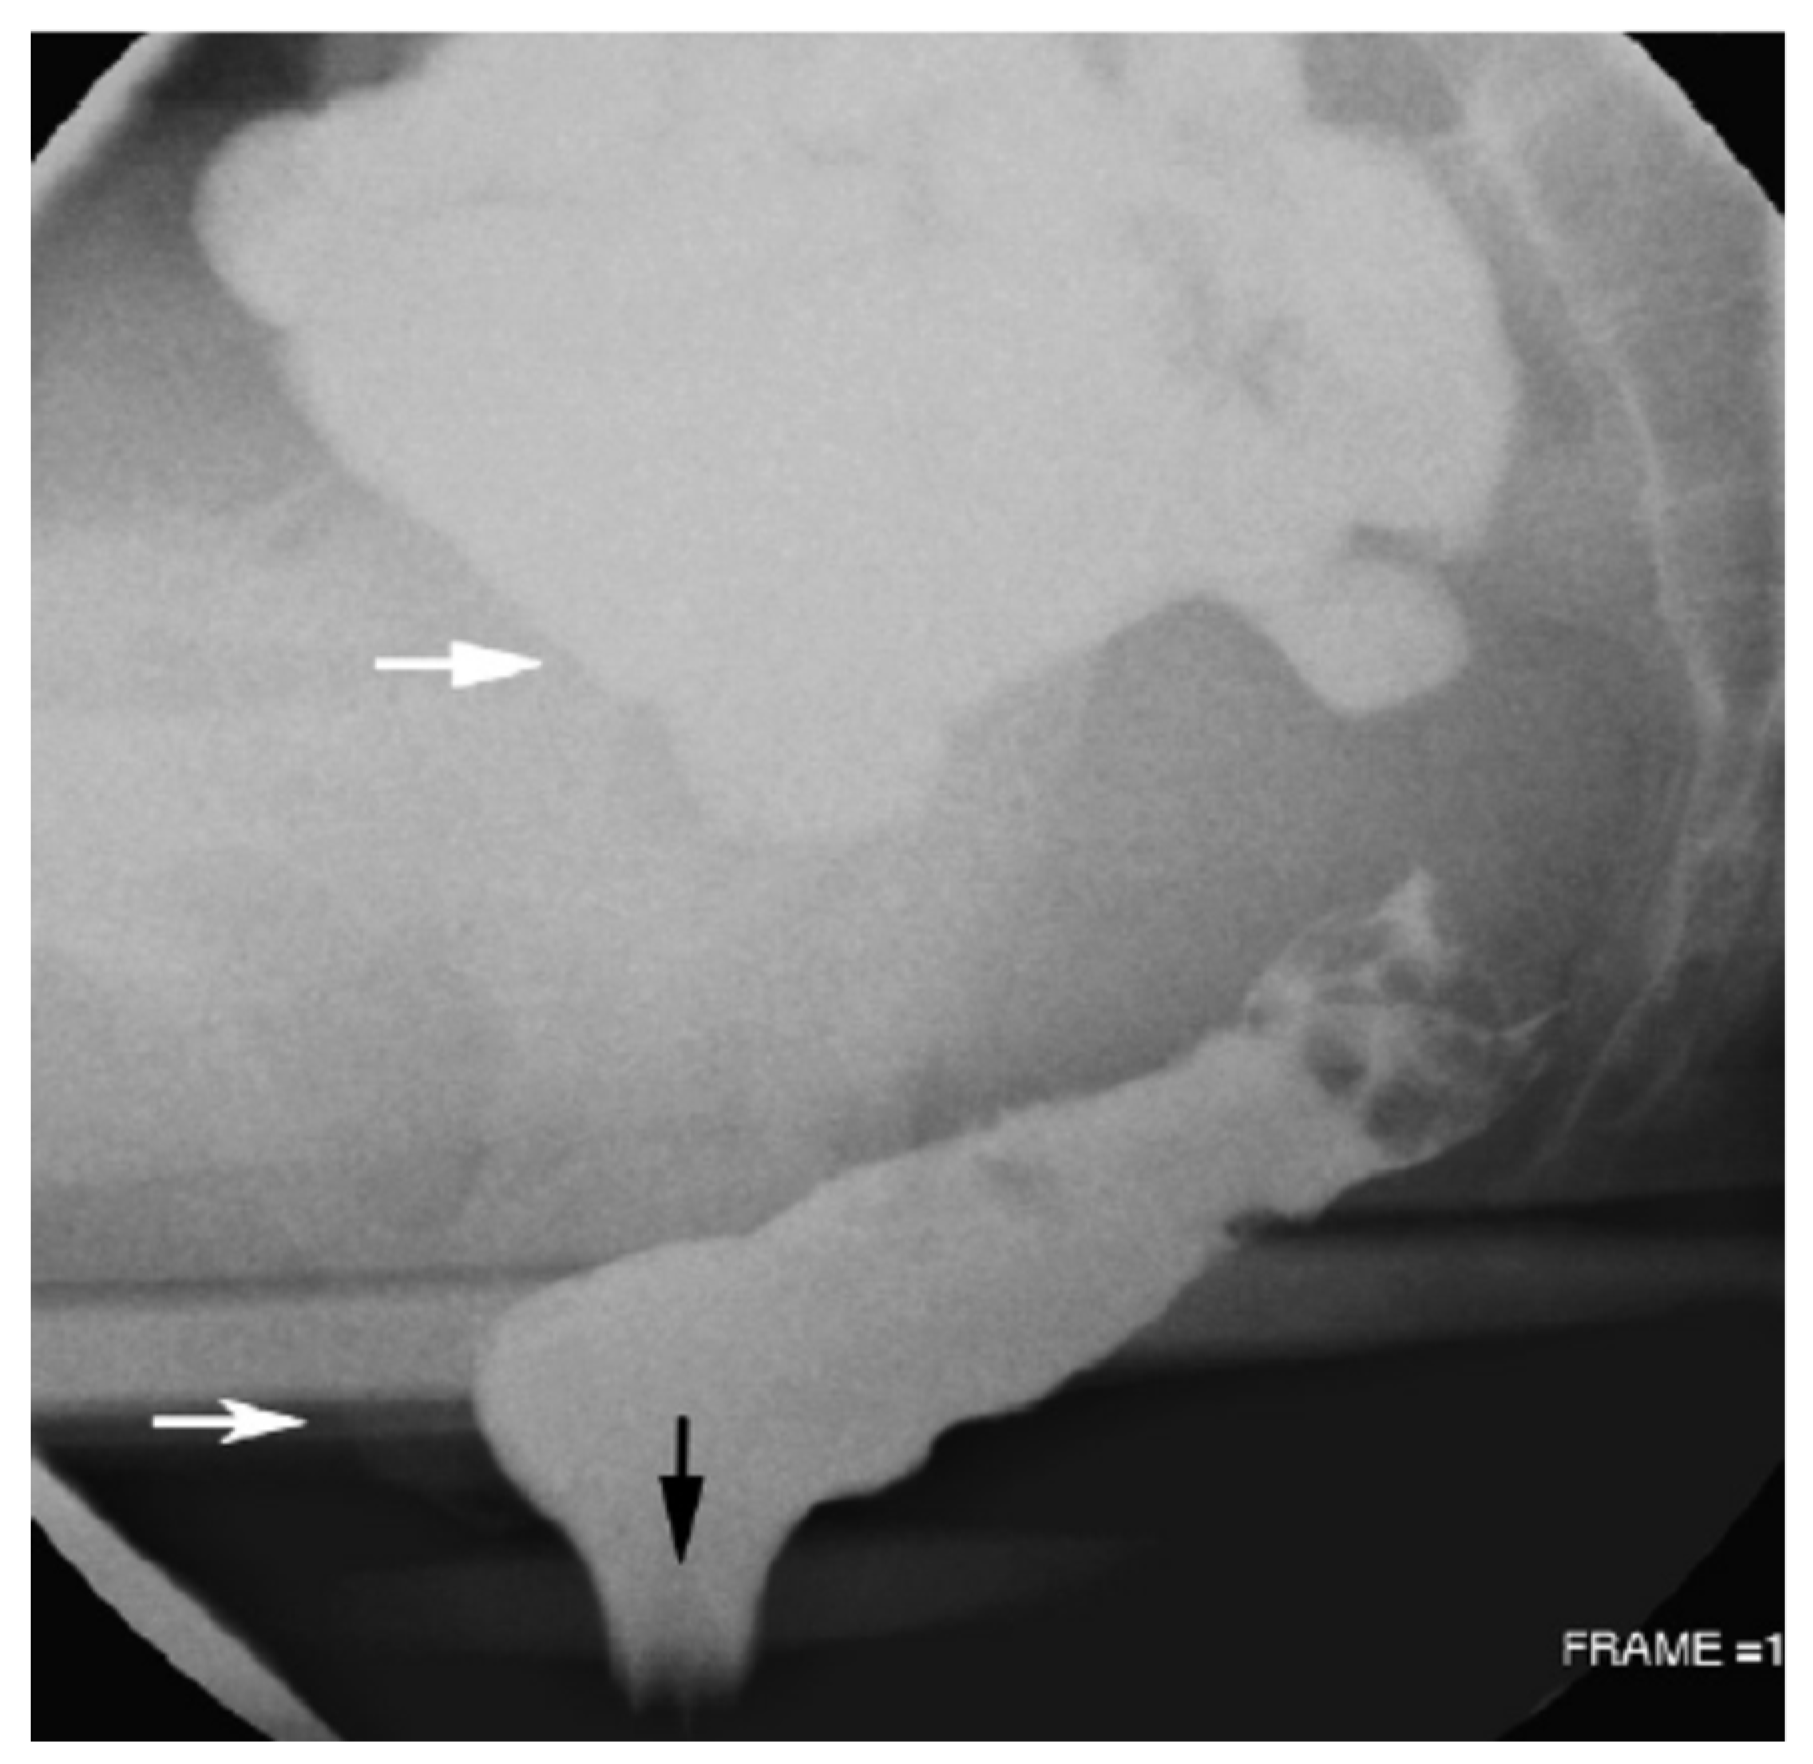

- Ganeshan, A.; Anderson, E.M.; Upponi, S.; Planner, A.C.; Slater, A.; Moore, N.; D’Costa, H.; Bungay, H. Imaging of obstructed defecation. Clin. Radiol. 2008, 63, 18–26. [Google Scholar] [CrossRef]

- Roos, J.E.; Weishaupt, D.; Wildermuth, S.; Willmann, J.K.; Marincek, B.; Hilfiker, P.R. Experience of 4 years with open MR defecography: Pictorial review of anorectal anatomy and disease. Radiographics 2002, 22, 817–832. [Google Scholar] [CrossRef]

- Lalwani, N.; El Sayed, R.F.; Kamath, A.; Lewis, S.; Arif, H.; Chernyak, V. Imaging and clinical assessment of functional defecatory disorders with emphasis on defecography. Abdom. Radiol. 2021, 46, 1323–1333. [Google Scholar] [CrossRef]

- Reginelli, A.; Di Grezia, G.; Gatta, G.; Iacobellis, F.; Rossi, C.; Giganti, M.; Coppolino, F.; Brunese, L. Role of conventional radiology and MRi defecography of pelvic floor hernias. BMC Surg. 2013, 13, S53. [Google Scholar] [CrossRef]